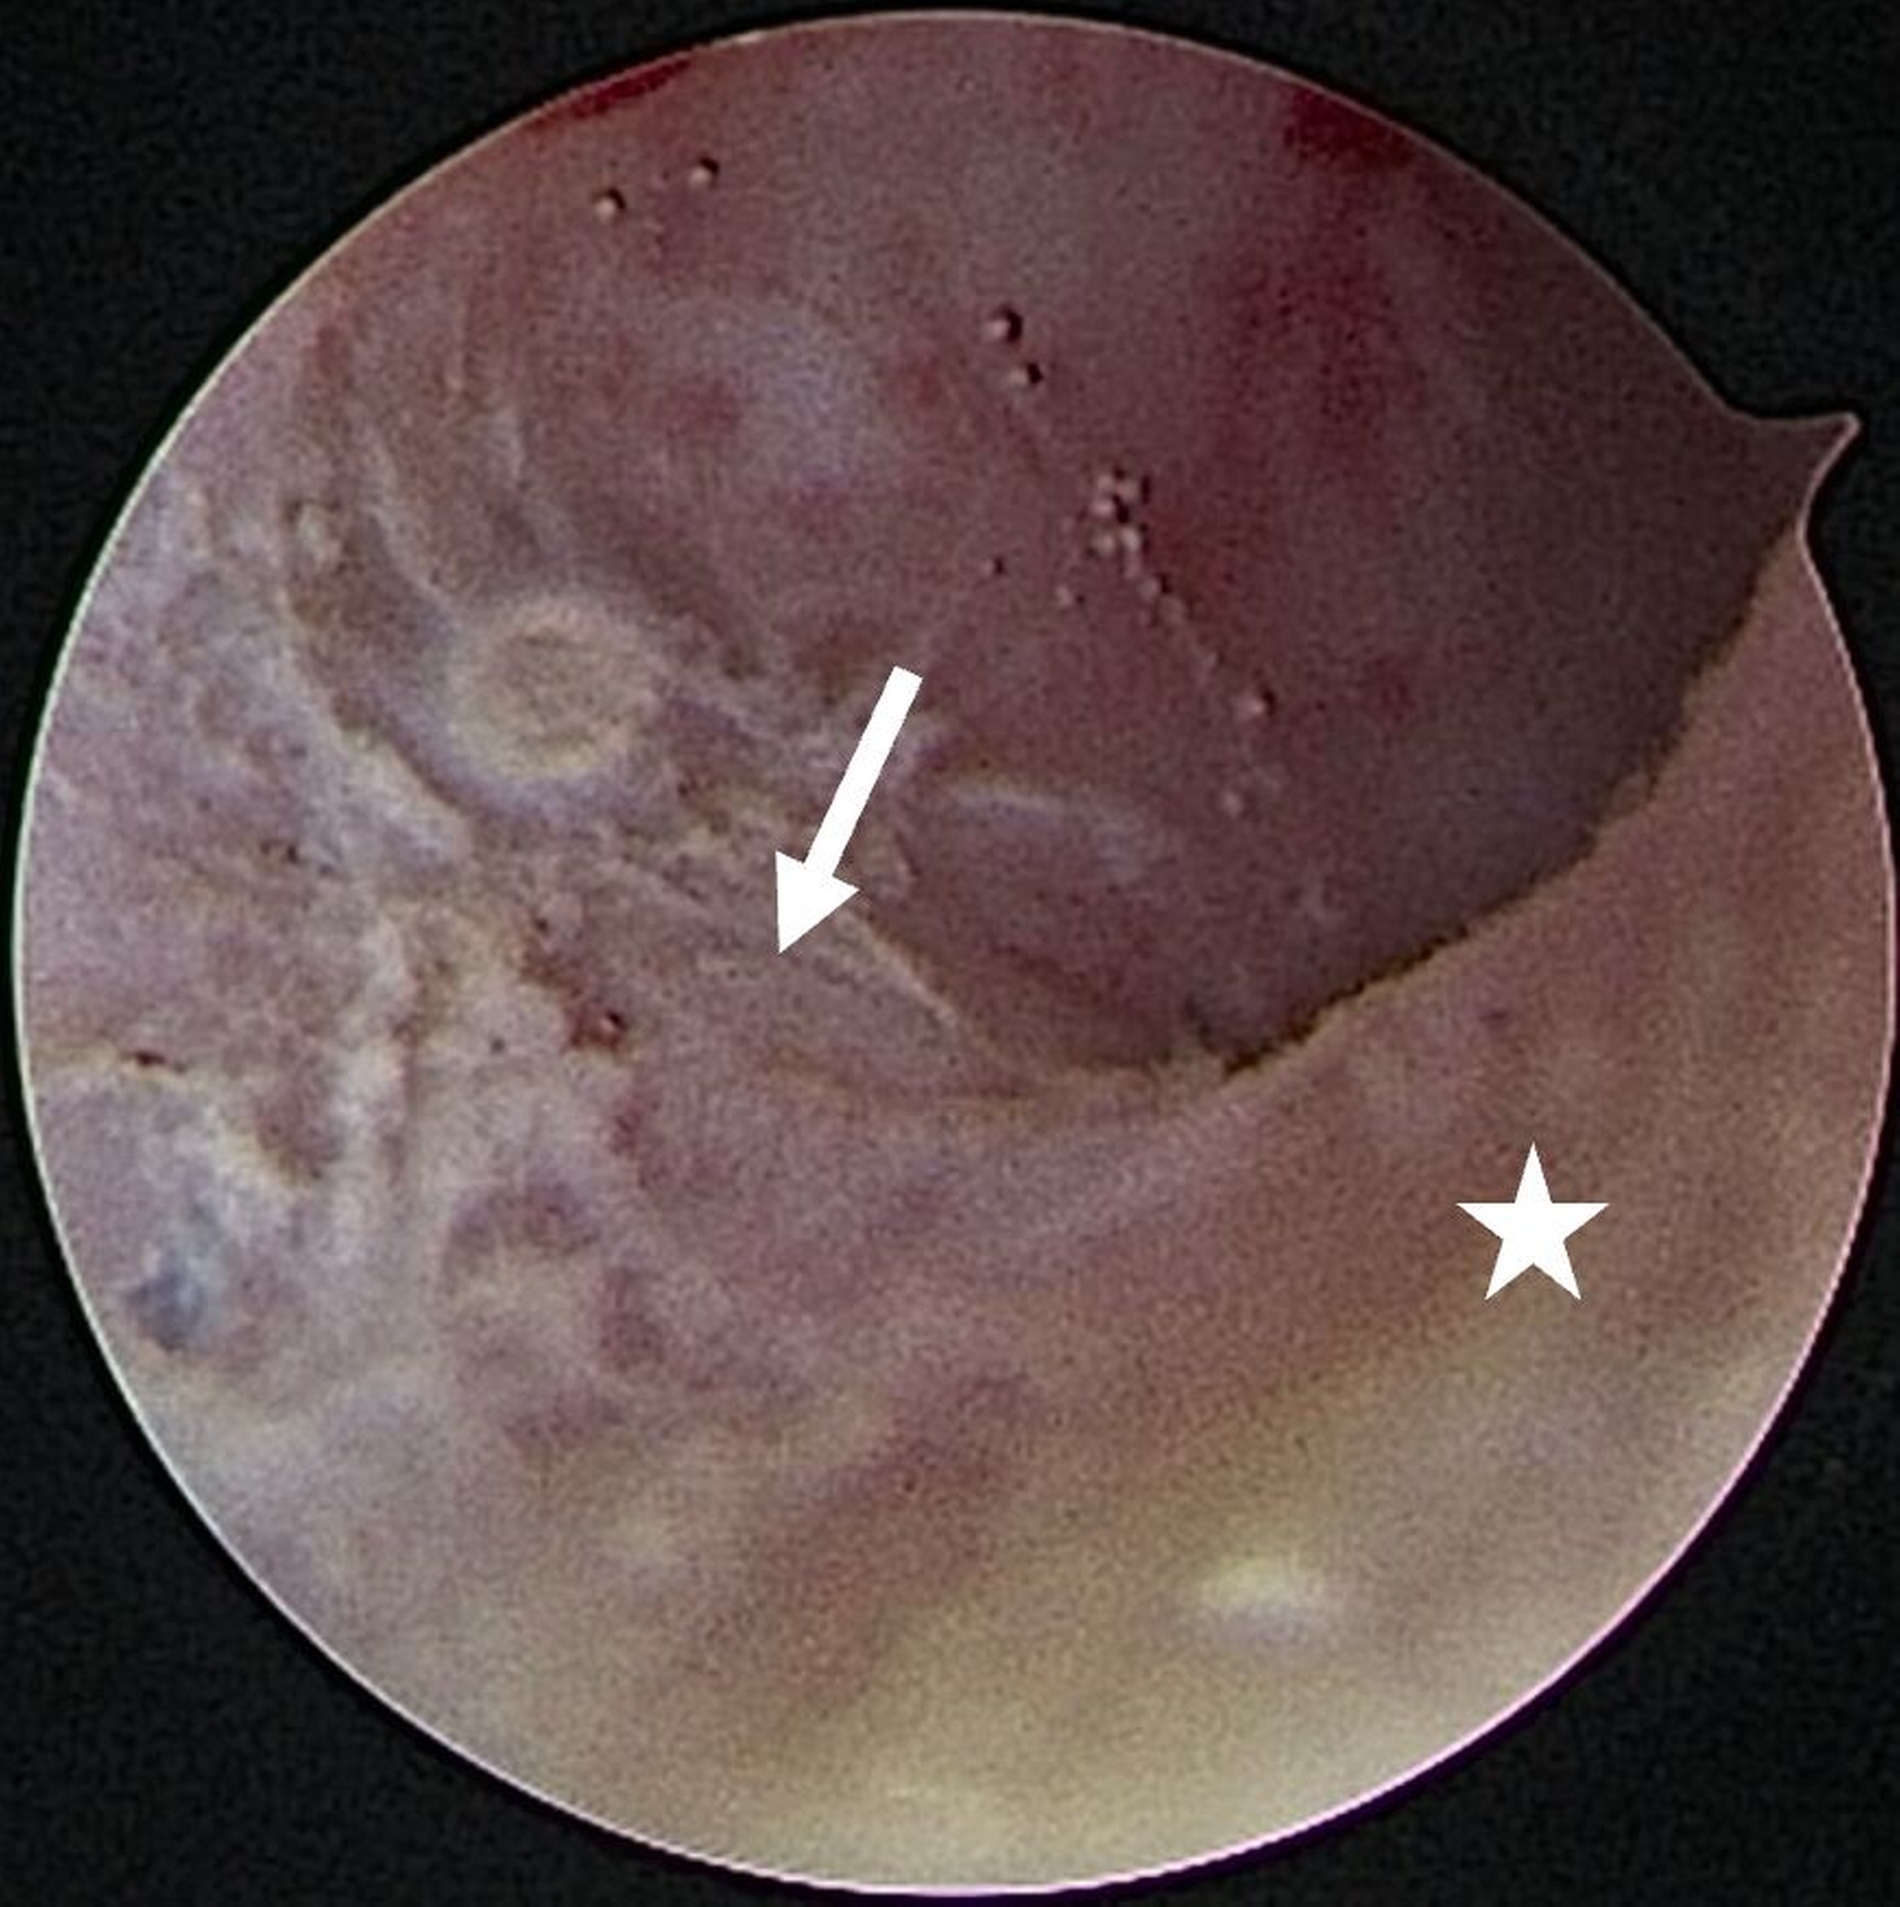

Eine Entzündung im Bereich der Gelenkkapsel (Synovitis) stellt eine häufige Ursache für arthrogen bedingte Beschwerden dar [Mercuri et al., 2025]. Neben der Darstellung des Gelenks und der Behandlung von Pathologien beruht ein positiver Effekt der Arthroskopie auf der Lavage des Gelenks. Dadurch können zum Beispiel proinflammatorische Mediatoren entfernt und intraartikuläre Adhäsionen gelöst werden [Soni, 2019]. Abbildung 2 zeigt die intraoperativen Befunde von zwei Patienten. Es wird jeweils der Übergang zwischen dem hinteren Aufhängungsband und der pars posterior des Discus articularis dargestellt.